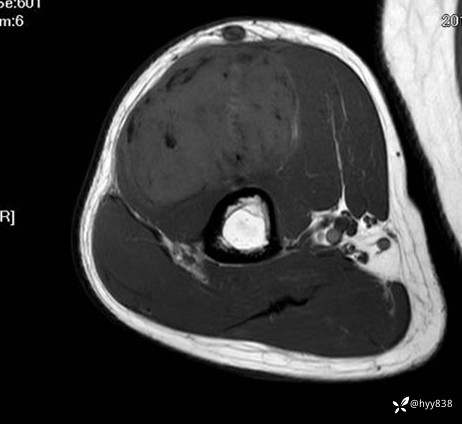

MRI AXI T1WI+T2WIfs

AXI T1WI+T2WIfs